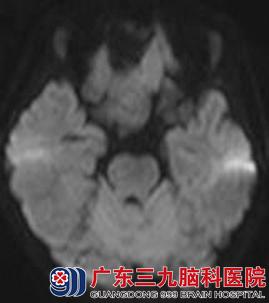

图5 弥散加权:病变呈等信号,其前方囊性部分呈低信号

CT表现(图1、2):前颅窝底可见一等密度(与脑实质密度相同)占位性病变,其前方可见囊性的低密度影,与脑脊液密度相似,相邻脑组织受推压,未见明显水肿密度影。MR表现(图3-6):病变呈等T1等T2信号,边界清晰;其前方可见长T1长T2信号影,增强后,病变未见强化。弥散加权成像(DWI):未见病变弥散受限,前方囊性部分呈低信号。考虑为前颅窝脑外占位性病变。